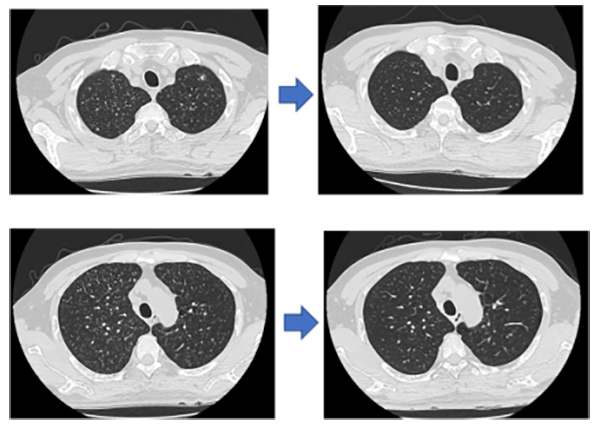

治疗的半年后,小姑娘和爸爸来复诊(图1),我终于看到,小姑娘不再使用激素的瓜子脸竟然这么清秀好看,不再有发热和咳嗽,吃得多睡得也香,身体的强壮和精神状态的好转让她变了一个人。爸爸还是一如既往地平静和温暖,微笑地对我说“都挺好都挺好”。

(图1 治疗前后患者胸部CT,经过治疗后,双肺多发粟粒样结节数量和面积均有明显减少)